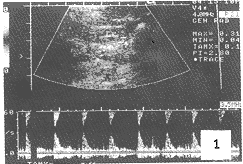

例1,患者,女性,18岁,因阴道持续流尿18年,于1997年7月17日入院。患者出生后除正常排尿外,有阴道持续滴尿,入院前每天需换裤5~6次。检查发现阴道不断流尿。超声检查:采用美国产Acuson128XP/10彩色多普勒血流显像仪,探头频率3MHz,患者取俯卧及侧卧位肾区扫查,右肾轮廓清楚,约120mm×57mm,内部结构正常,肾血流显示丰富呈树枝状分布。多普勒测量肾动脉血流,收缩期最大血流速度(SMAX)为0.65m.s-1,舒张期最小血流速度(DMIN)为0.22m.s-1;阻力指数(RI)为0.66,SMAX/DMIN(S/D)值为2.95。左肾床区未见肾影,取仰卧位腹部扫查,在腹主动脉左旁L4-5水平见一小肾结构为36mm×28mm轮廓模糊,肾血流稀少。肾动脉血流测量,MAX为0.31m.s-1;MIN为0.04m.s-1;RI为0.87;S/D为7.75(图1)。同时在耻骨上扫查,膀胱充盈佳,透声好,膀胱左后方见一长37mm,宽10mm的管道与阴道壁贯通(图2)。诊断:①异位先天性左肾发育不良(供血减少),②左输尿管异位开口——入阴道,③右肾代偿性增大,经膀胱镜检查证实。7月29日在硬膜外麻下行左腹膜后手术探查,在腹膜后找到左输尿管并切开,向下插入输尿管导管,注入美兰后阴道内尿液蓝染,游离出肾脏约30mm×25mm×20mm,皮质薄,肾盂扩大为囊状,行左肾切除。病检报告为左肾发育畸形(小肾脏)。术后无阴道漏尿。

图1 腹主动脉左旁见一小肾畸形,多普勒显示肾动脉血流频谱呈高阻型

Fig. 1 A little abnormal kidney at the left of the abdominal aorta, and the spectral display of the kidney artery is evidenced as the high resistence type by the doppler ultrasonic examination